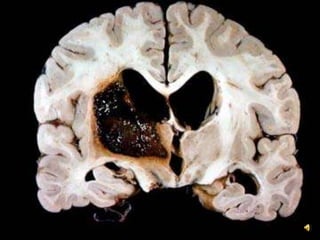

Left (Dominant) Hemisphere Stroke: ClinicalAphasiaRighthemiparesisRight-sided sensory loss Right visual field defect Poor right conjugate gaze Dysarthria Difficulty reading, writing, or calculatingL affect RDiagnosis: Recent cerebral infarction in left MCA distribution.Left cerebral hemisphere shows swelling with compression of the lateral ventricle mainly in the frontal area, due to recent infarct in the Middle Cerebral Artery (MCA) distribution. The brain in the MCA area shows discoloration of the cortex and also blurring between the cortex and white matter.

Left (Dominant) HemisphereStroke: ClinicalAphasiaRighthemiparesisRight-sided sensory loss Right visual field defect Poor right conjugate gaze Dysarthria Difficulty reading, writing, or calculatingL affect RDiagnosis: Recent cerebral infarction in left MCA distribution.Left cerebral hemisphere shows swelling with compression of the lateral ventricle mainly in the frontal area, due to recent infarct in the Middle Cerebral Artery (MCA) distribution. The brain in the MCA area shows discoloration of the cortex and also blurring between the cortex and white matter.